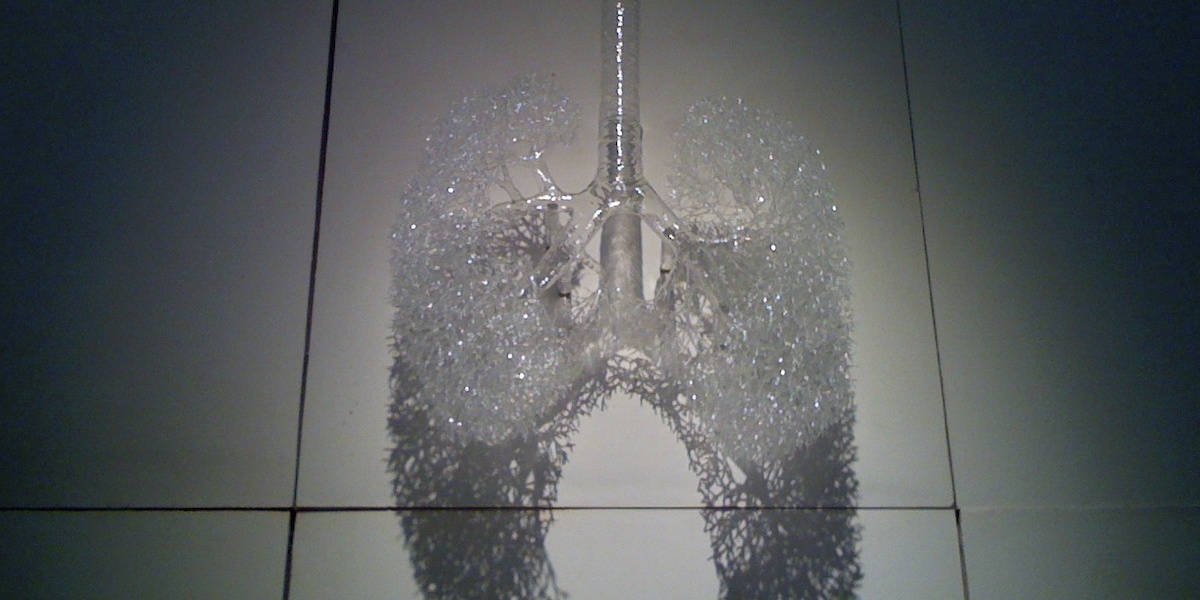

Knowing how lungs work matters for personal choices, public policy, and medical innovation. Lungs are finely tuned organs that trade oxygen and carbon dioxide across a vast microscopic surface, fend off inhaled particles with built-in cleaning systems, and rely on precise blood flow to do their job. When those systems fail—because of smoke, infection, or pollution—the consequences ripple through communities and health systems.

The lungs are built for two complementary jobs: maximize the surface for gas exchange, and keep that surface clean and well perfused. Below you’ll find three related themes: the alveolar surface area that enables rapid oxygen uptake; the mucociliary clearance system that removes particles and microbes; and the lung’s specialized blood supply that makes diffusion extremely efficient. These basics set the stage for the numbered facts that follow.

1. Lungs have an enormous surface area — about the size of a tennis court

The inner surface area of healthy adult lungs is roughly 60–80 square meters, comparable to a tennis court. That area comes from about 300 million alveoli, tiny sacs where oxygen and carbon dioxide pass between air and blood.

A large exchange surface speeds diffusion, so oxygen gets into blood quickly and carbon dioxide is expelled efficiently. Endurance athletes and people living at altitude depend on this capacity; when demand rises, the same surface area supports much higher gas transfer rates.

To picture the scale: your alveoli folded out would cover roughly a tennis court or about half a badminton court—remarkable for organs tucked inside a ribcage.